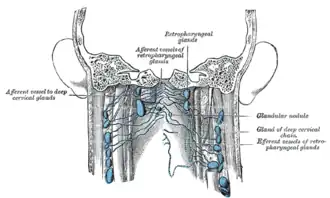

Additional images

-

Lymphatics of pharynx.

Lymphatics of pharynx. -